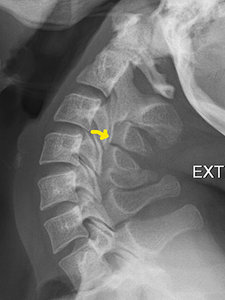

FIG 2 Extension C Spine

Case in point: A patient experienced ongoing pain in the neck radiating into the traps with intermittent headaches as a result of a whiplash injury from an auto accident eight months ago. The MRI was normal, as was the cervical spine study, except for intersegmental instability at the C3-4 motor unit, which indicates biomechanical hypermobility. This finding was not demonstrated on the MRI. (Figures 1-3)

Yes, it is possible to visualize a frank tear of the small intersegmental ligamentous structures on an MRI, but simple flexion and extension radiographs will demonstrate this type of intersegmental instability clearly, along with the biomechanical changes of associated articulations. There are MR units that can perform flexion and extension of the cervical spine and weight-bearing studies, but they are not generally available, are expensive, and the quality of the images may not be as good as the higher field strength units.1